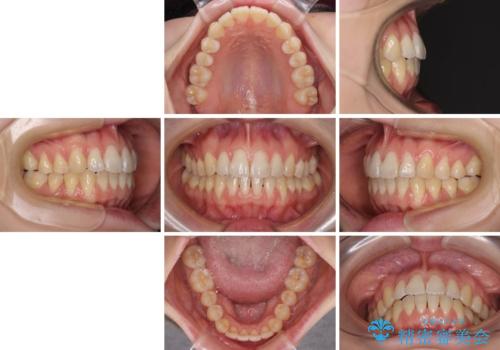

気になるデコボコとオープンバイト インビザラインでの矯正治療

- 治療期間

- 1年10ヶ月

オープンバイトは容易に後戻りを起こすため、少しでも後戻りリスクを軽減するために舌癖改善のトレーニングをしっかりと行っていただきました。